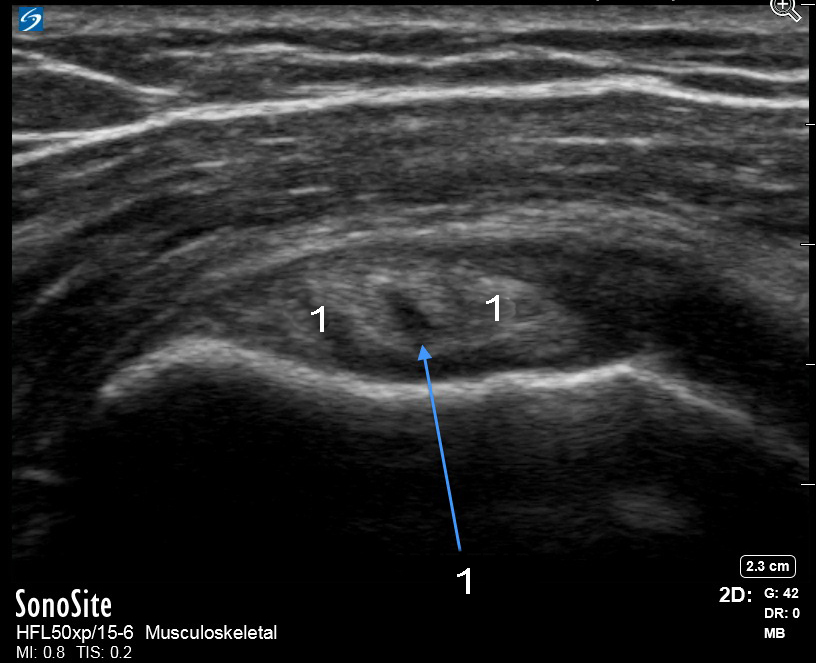

Imagen con zoom de rotura del tendón del bíceps del hombro

Rotura

Tendón del bíceps (TB)